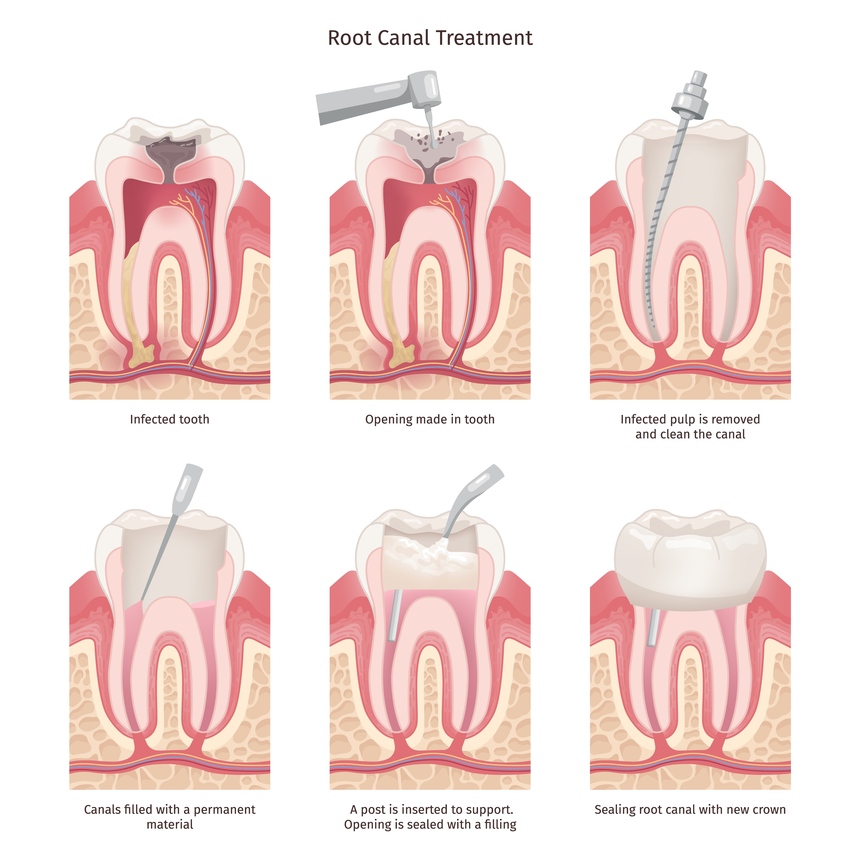

Painless Root Canal Treatment in College Road Nashik

A root canal is a dental procedure designed to treat infected or damaged tooth pulp. Traditionally associated with disco...

Painless Root Canal Treatment in Canada Corner Nashik

A root canal treatment is often associated with pain and discomfort, but modern dental advancements have made it a painl...